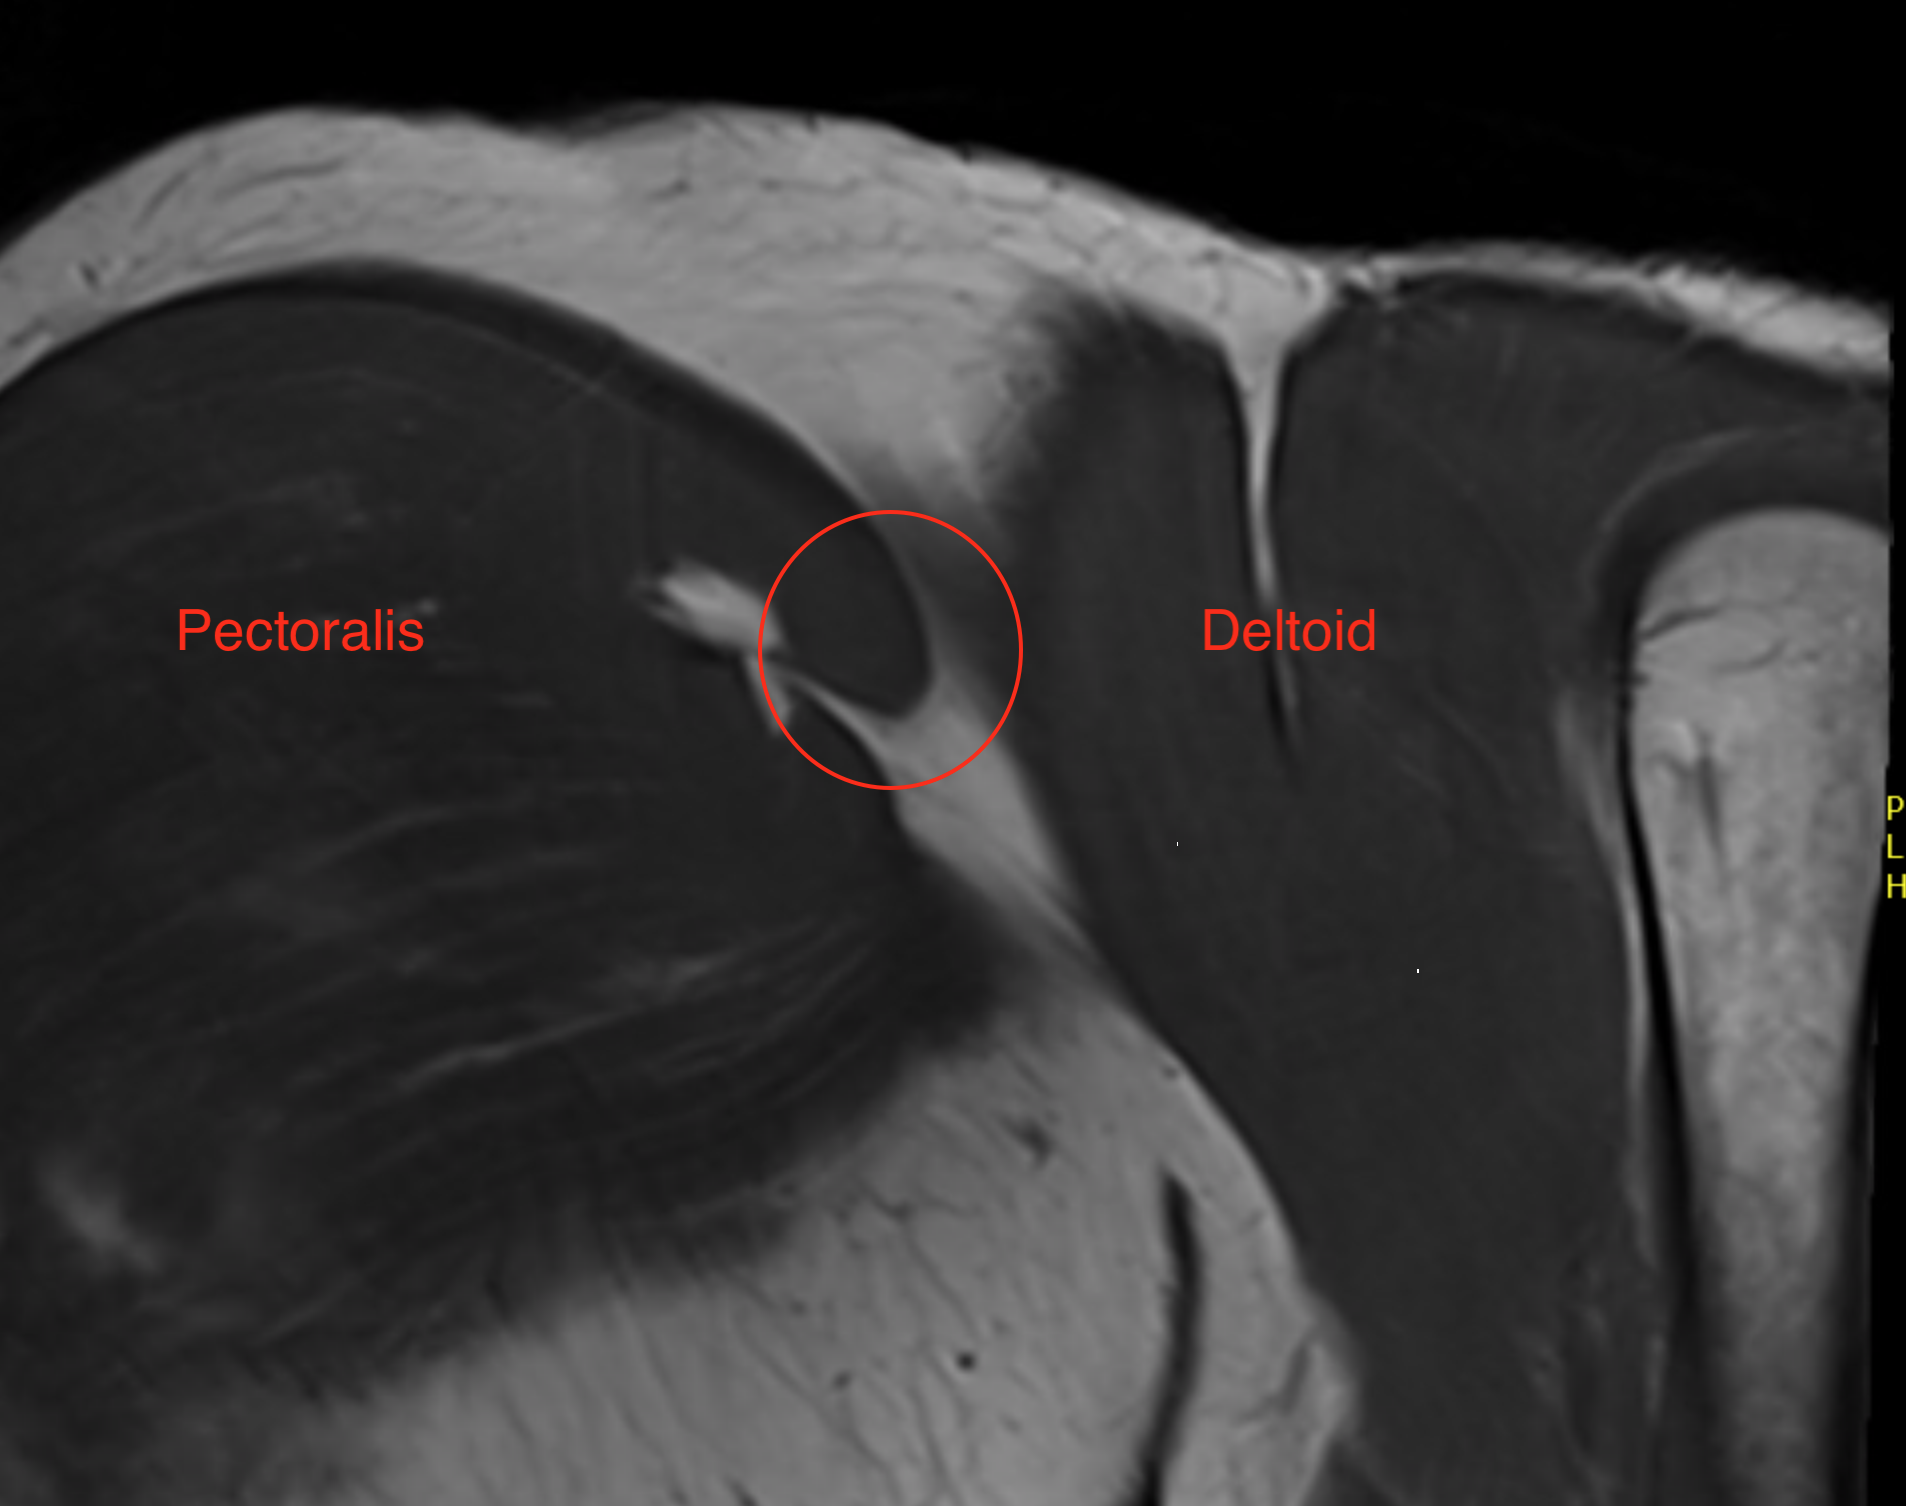

Axial T2 Right shoulder demonstrating tendon avulsion of both sternal and clavicular heads